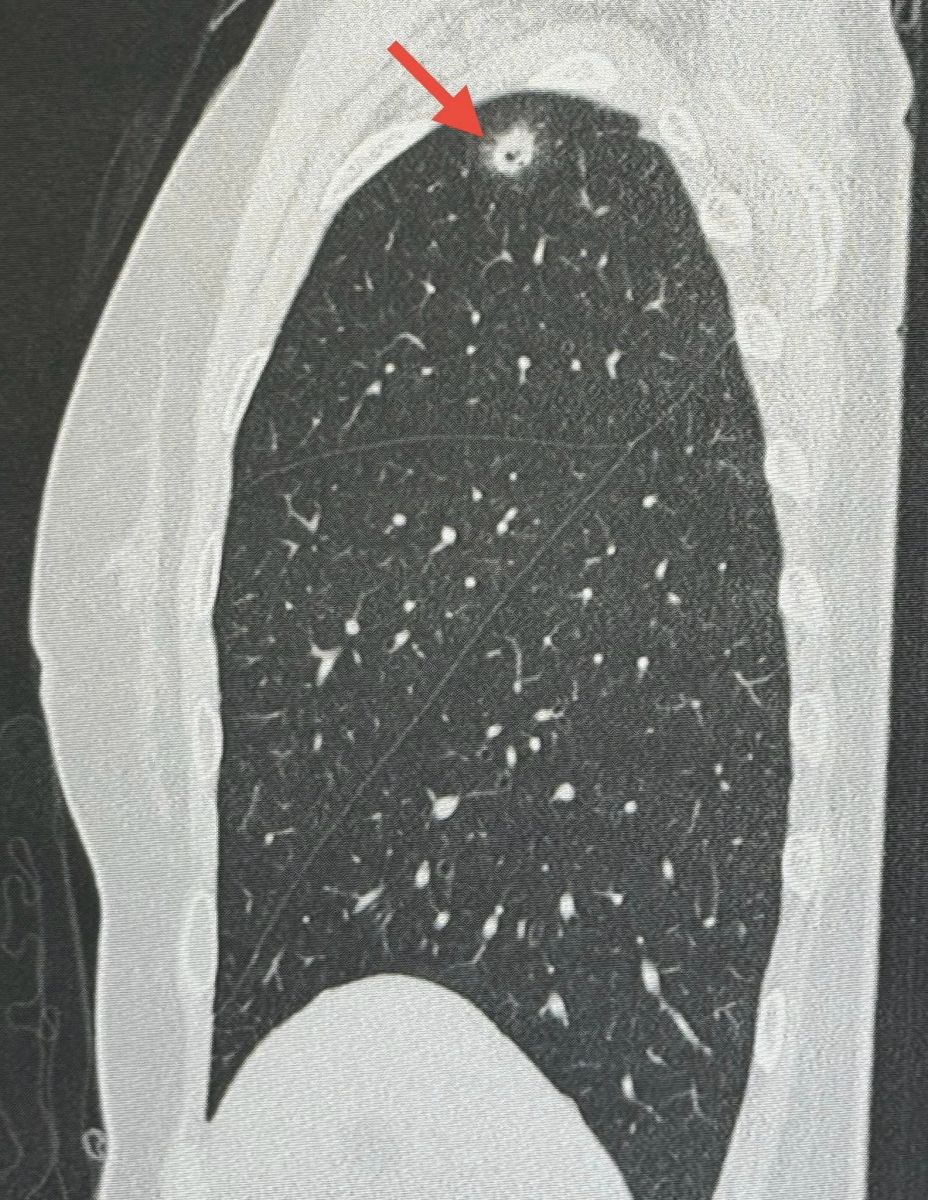

3 มิ.ย. 2567 นพ.มนูญ ลีเชวงวงศ์ ผู้เชี่ยวชาญด้านโรคระบบทางเดินหายใจ ได้โพสต์เฟซบุ๊กระบุว่า "ผู้ป่วยหญิงอายุ 52 ปี บ้านอยู่ กทม. ปกติแข็งแรงดี ไม่ไอ ไม่มีไข้ ไม่เบื่ออาหาร น้ำหนักไม่ลด ไม่ปวดหัว ไม่เคยสูบบุหรี่ ไม่มีโรคประจำตัว ไปตรวจร่างกายประจำปี วันที่ 12 พฤษภาคม 2567 เอกซเรย์ปอดพบก้อนเล็กๆเกิดขึ้นใหม่ที่ปอดขวากลีบบน เอกซเรย์ปอดก่อนหน้านั้น 1 ปีปกติ ทำคอมพิวเตอร์ปอดพบก้อนขนาด 0.9 × 0.9 × 1.7 เซนติเมตร เห็นโพรงอยู่ข้างในก้อนที่ปอดขวากลีบบน ตรวจเลือดไม่ติดเชื้อเอชไอวี ผู้ป่วยไปรับการผ่าตัดปอดเอาก้อนจากปอดขวากลีบบนออกที่โรงพยาบาลใกล้บ้านเมื่อวันที่ 22 พฤษภาคมเพราะสงสัยมะเร็งปอด ผลพยาธิวิทยาเป็นปอดอักเสบจากเชื้อราคริปโตคอคคัส ตรวจเลือดหาคริปโตคอคคัสแอนติเจนหลังผ่าตัด 4 วันให้ผลบวก titer 1:8 แพทย์เริ่มให้การรักษาด้วยยา fluconazole ผู้ป่วยมาขอคำแนะนำหลังจากนี้ควรทำอย่างไรต่อไป

ซักประวัติ มีนกพิราบอยู่แถวบ้านหลายตัว ให้อาหารนกพิราบประจำ ผู้ป่วยรายนี้หายใจสปอร์ของเชื้อราคริปโตคอคคัส นีโอฟอร์แมนส์ (Cryptococcus Neoformans) จากมูลนกพิราบเข้าไปในปอด ทำให้เกิดปอดอักเสบเป็นก้อนที่มีโพรงข้างใน โชคดีที่เชื้อราไม่ได้กระจายออกนอกปอดเนื่องจากร่างกายแข็งแรง มีภูมิคุ้มกันดี วางแผนให้ยาฆ่าเชื้อราฟลูโคนาโซลชนิดกินต่อไปประมาณ 6 เดือน แนะนำให้อยู่ห่าง และหลีกเลี่ยงให้อาหารนกพิราบ"